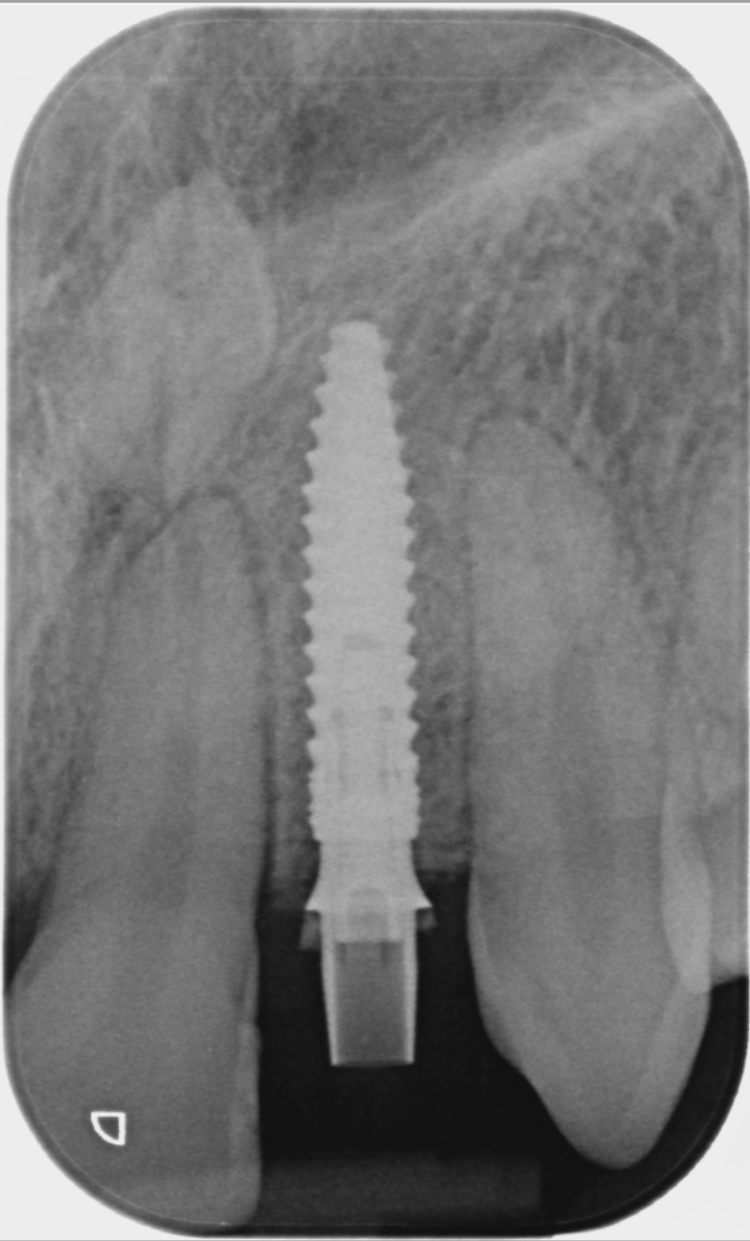

A CBCT scan was taken using a Morita X800. This dataset was imported into the planning software, where it was merged with the STLs of the anatomically correct diagnostic digital wax-up and modules.  With the anatomically correct diagnostic wax-up, there was no ambiguity regarding planning the implant position, angle and depth with precision. I like to plan these types of cases myself, but it is possible to outsource the planning stage for clinicians who are new to the process and looking to increase their workflow efficiency. For this case, I wanted to build up the gingival thickness in order to improve the papillae around the implant sites. The surgical plan, therefore, included soft tissue grafting.

On the day of surgery, a split-thickness envelope flap was raised. Two CONELOG® Progressive-Line implants were placed through the surgical guide in the pre-determined lateral incisor positions. Soft tissue augmentation was performed simultaneously with the implant placement, and the site was sutured and closed without tension. The implants were immediately loaded using provisional crowns that were pre-fabricated in the lab.

The CONELOG implants were selected because they provide a very stable connection and feature a geometry that facilitates high primary stability, which is important when placing immediate implants. They also integrate very successfully – we have had better results with these implants than with other products that are available. I also appreciate the simplicity of the keyless guided surgery kit.